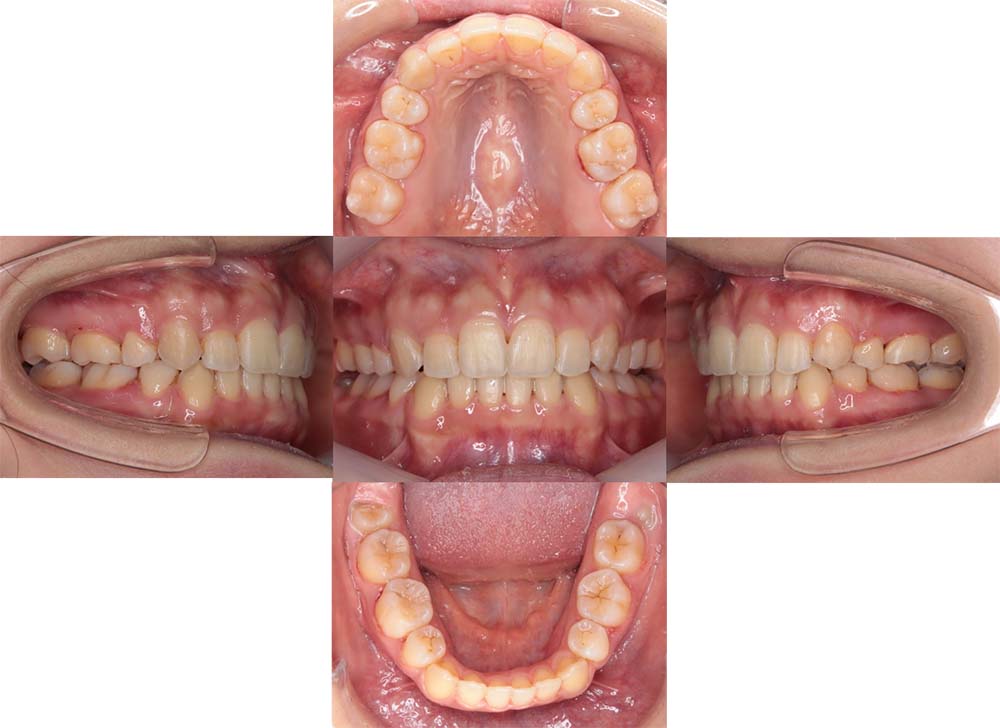

症例04

| 主訴 | 歯並びのガタガタと出っ歯が気になる。 |

| 診断名あるいは主な症状 | 上顎前突、叢生 |

| 年齢/性別 | 16歳・女性 |

| 矯正ステージ | 大人の矯正治療 |

| 治療方法 | ワイヤー矯正 |

| 抜歯部位/抜歯有無 | 抜歯 |

| 治療内容 | 抜歯したスペースを使用し、ガタガタの改善と上下顎前歯を後退させた。 |

| 費用 |

85万円程度(2025.10時点の料金となります。) ※矯正基本料金、審美ブラケットを含む |

| 治療期間 | 2年5ヶ月 |

| 主なリスク・副作用 | 痛み、歯根吸収、歯肉退縮、虫歯、後戻り |